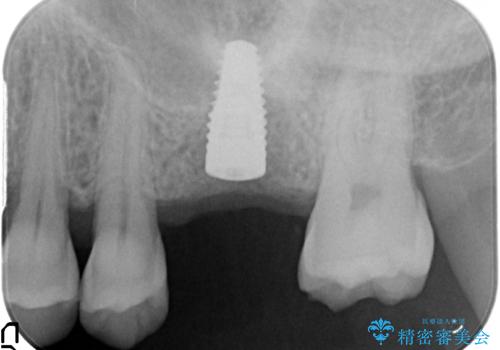

- 歯が割れてしまい、抜歯後のインプラント治療を希望され相談来院されました。

歯の喪失後に失われた咬合機能を回復するため、ブリッジ・入れ歯・インプラントの治療提案を行いました。

それぞれの長短所を検討し、隣接する歯を削らずにすみ、咬合機能をもっともしっかり回復できるインプラント治療を希望されました。

歯が割れるほどの咬合力が強い方でしたので、3本の歯を2本で支えるブリッジではなく、咬合負担能力の増えるインプラント治療にメリットが大きいと言えます。